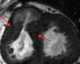

Subvalvular left ventricular aneurysm